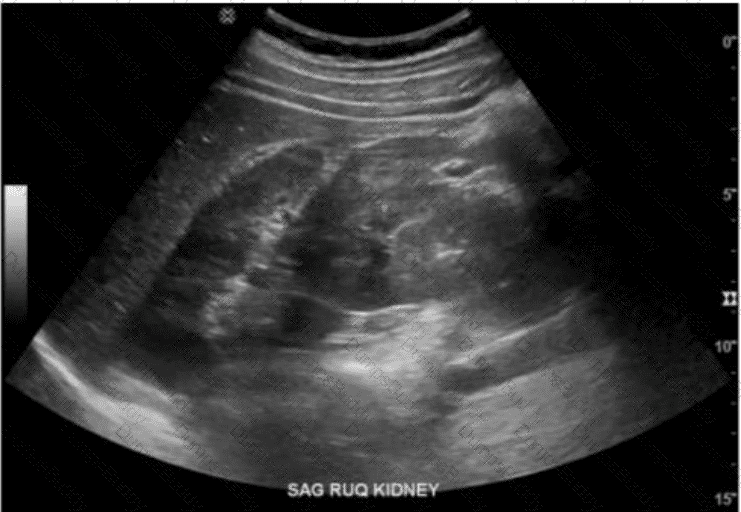

Which abnormality is depicted in this image of a patient who presents with a fever following a liver biopsy?